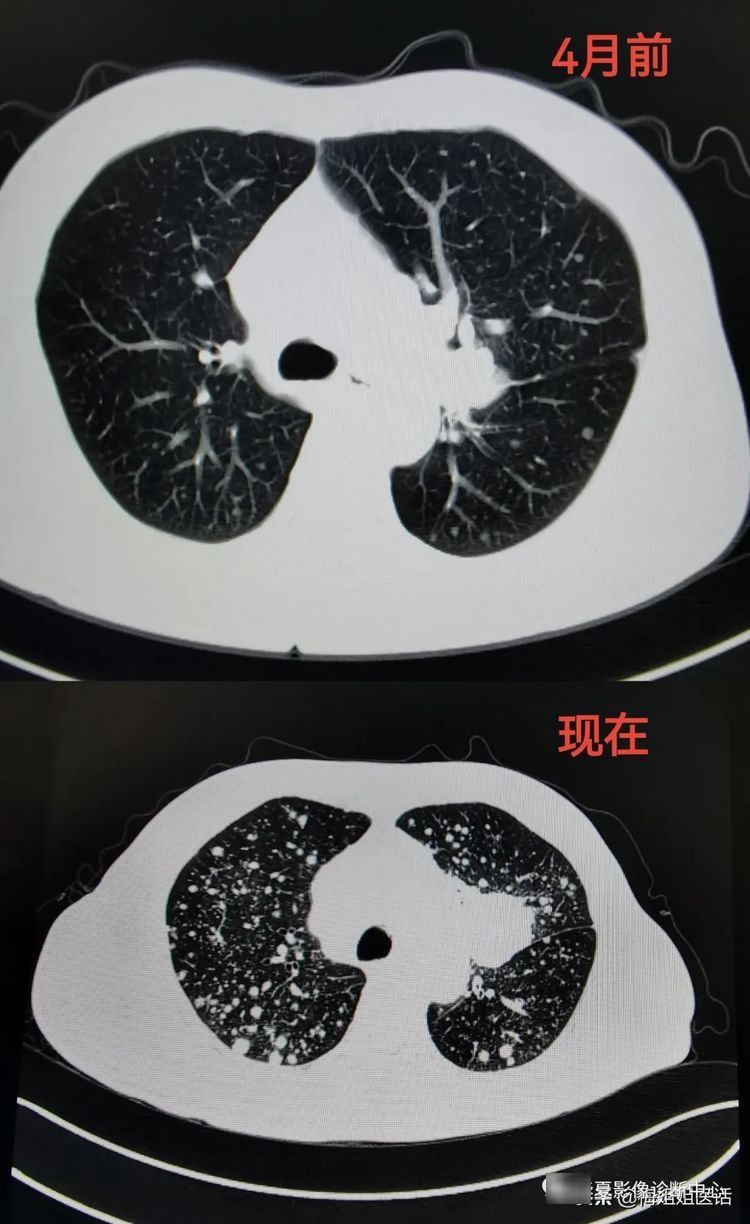

从肺部包块到肺癌,包块长大并出现肺内转移

双肺出现的多个转移病灶

上面三张CT影像图片,显示了患者从10个月前发现左肺病灶。病变逐渐长大并侵袭更多器官的影像变化过程。

看着患者正常的肺在这10个月里逐渐被像满天星一样星星点点的白色病灶蚕食。很有些遗憾。